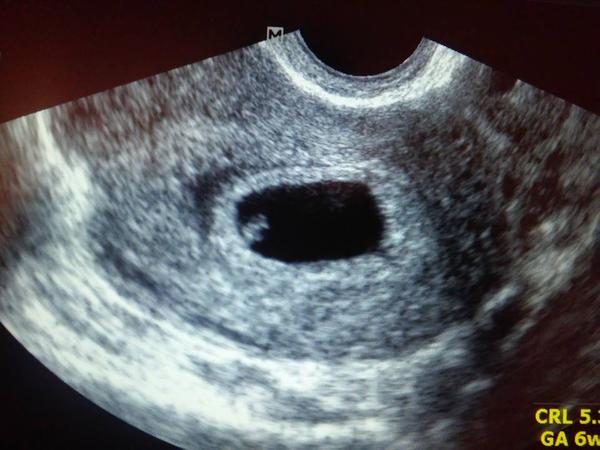

@meli8412 Super,tak to teda riadne rastie 🙂 môj mal dneska na 6+2 5,3mm 🙂 Áno,teraz som si všimla že som napísala 13TT.písala som na mobile zrejme som ťukla vedľa,viem že do 12.tt sa berie 😀 Myslím si,že nespravím nič zlé ak ho budem užívať aj naďalej 😕 Držím palce nech vídu dobré výsledky! My máme len takúto fotku aj to len mobilom sme si odfotili,lebo dr.nemal tlačiareň 😀